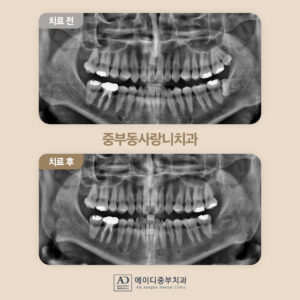

정밀한 검사를 위해

파노라마 사진을 촬영해 보았더니

아래턱 왼쪽 사랑니(#38)는

완전 매복 상태로

잇몸뼈 속에 묻혀

바로 앞의 두 번째 큰 어금니(#37)의

뿌리를 자극하고 있었습니다.

위턱 왼쪽 사랑니(#28)는

정상적으로 맹출은 하였지만

안쪽에 위치해 있다 보니

위생관리가 잘되지 않고 있었는데요.

깔끔하게 발치가 마무리된

파노라마 사진입니다.